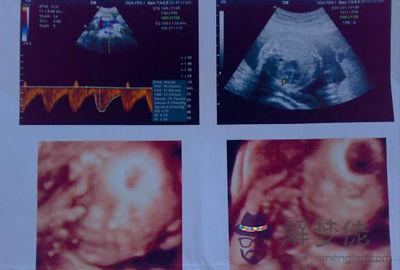

四維彩超主要是用來檢查胎兒發育是否正常,排除胎兒發育畸形的檢查項目。首先四維彩超主要檢查的是面部畸形,四維彩超檢查時會重點觀察胎兒雙眼與眼眶是否等大等圓以及眼距的測量。再就是可以詳細觀察軟腭以及硬腭,上唇弧型曲線是否連續四維單子上3個亮點是男孩。

四維彩超主要是用來檢查胎兒發育是否正常,排除胎兒發育畸形的檢查項目。首先四維彩超主要檢查的是面部畸形,四維彩超檢查時會重點觀察胎兒雙眼與眼眶是否等大等圓以及眼距的測量。再就是可以詳細觀察軟腭以及硬腭,上唇弧型曲線是否連續生兒子的四維彩超圖片。